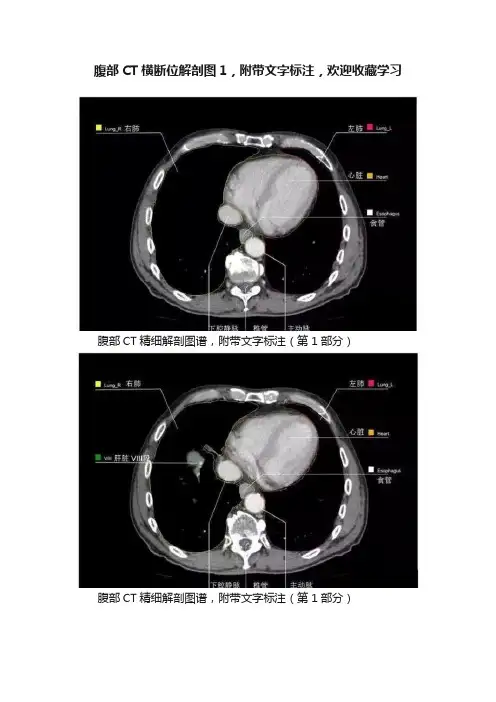

腹部CT横断位解剖图1,附带文字标注,欢迎收藏学习

腹部CT精细解剖图谱,附带文字标注(第1部分)